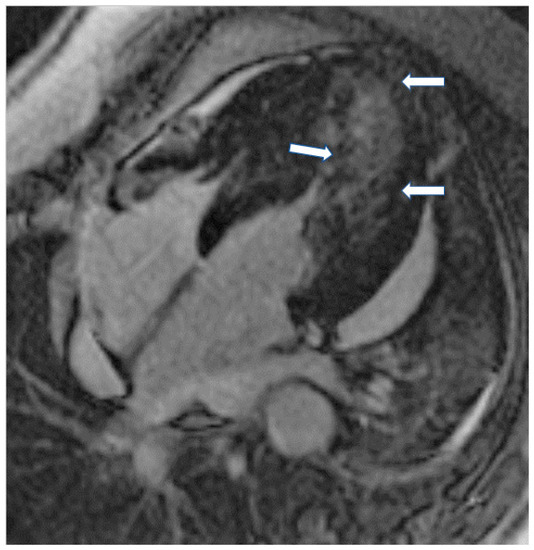

The presence of LGE in HCM, usually in the hypertrophic area, is a high-risk feature, and its presence should be used as a marker for major adverse outcomes such as sudden cardiac death (SCD), arrhythmias, and failure (HF) (Figure 4). It should be also included as an additional index in decision making for implantable cardioverter defibrillators for primary prevention [64]. LGE is usually present in segments with hypertrophy, in some end-stage cases, some segments may appear thinned with transmural fibrosis. The extent of LGE can be quantified either as a sum of the enhanced areas measured in grams or as a proportion of the total left ventricular mass (percentage of LGE). The percentage of fibrosis varies according to the quantification method used. From those methods, the only validated method against necropsy is the semi-automatic 2-standard-deviation technique, which consists of defining LGE as a 2-standard deviation above the mean signal intensity of the distant myocardium and constitutes the preferred quantification method. LGE is rarely observed in mutation carriers without LVH. In a study including patients with pathogenic sarcomere mutations and hypertrophic cardiomyopathy, subjects with mutations but no LV hypertrophy, and controls, CMR showed LGE in 71% of subjects with overt hypertrophy but in none of the mutation carriers without hypertrophy. Different studies have shown an increase in the risk of ventricular arrhythmias in patients with HCM related to the presence of fibrosis evaluated by LGE in comparison with individuals without LGE [63].

Figure 4.

Four chamber inversion recovery image showing severe hypertrophy and extensive LGE (arrows).